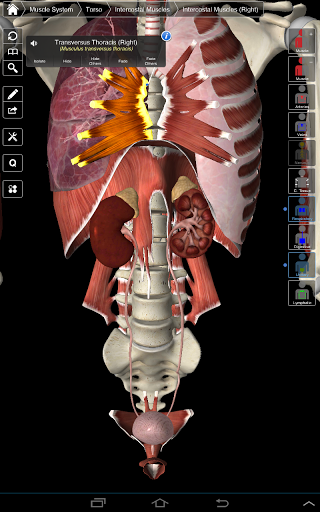

Основна анатомія 3 - це найновіша технологія та новаторський дизайн. Ріжучий 3D-графічний движок, зроблений на замовлення 3D4Medical з усього світу, наділений високоінформативною анатомічною моделлю і забезпечує високу якість графіки, яку не може досягти ніхто інший конкурент.

Програма являє собою унікальний підхід до вивчення загальної анатомії. Графіка не має аналогів і навчається, використовуючи інформативний контент та інноваційні функції, багатий та захоплюючий досвід.

НОВІ 3D-ТЕХНОЛОГІЇ

Основна Анатомія 3 чутлива, візуально приголомшлива і легка. Додаток повністю 3D, що означає, що ви можете переглядати будь-яку анатомічну структуру окремо, а також з будь-якого кута.

Безперервна навігація та функціональність

Розумна функціональність, знайдена в додатку, дозволяє користувачеві знімати шари м'язів за допомогою інструмента «скальпель». Ця програма надає користувачам можливість увімкнення / вимкнення систем без необхідності скасувати вибір окремих структур або переплутати через безліч попередньо визначених регіональних вкладок, як і інші програми.

---- Більше 4000 дуже детальних анатомічних структур